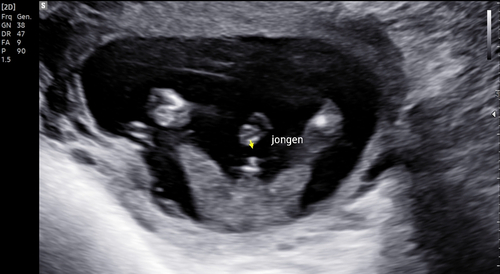

Dit is geen nub meer, dit is gewoon het geslacht van de baby voor degenen die dat kunnen zien.

Dit is geen nub.

Inderdaad deze echo laat echt het geslacht zien.